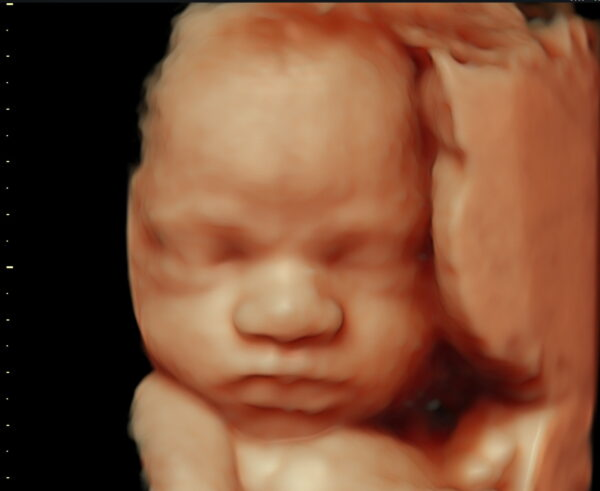

Een 3D/4D HD live echo is alsof je een kijkje neemt in de buik. Bij Baby’s World is het mogelijk om een vroege 3/4D pretecho te maken tussen 13 en 19 weken zwangerschap. Vanaf 20 – 34 weken zwangerschap is het mogelijk om het gezicht van jouw kindje goed in beeld te krijgen met een 3/4D pretecho. De beste periode is tussen de 24 en 30 weken zwangerschap.